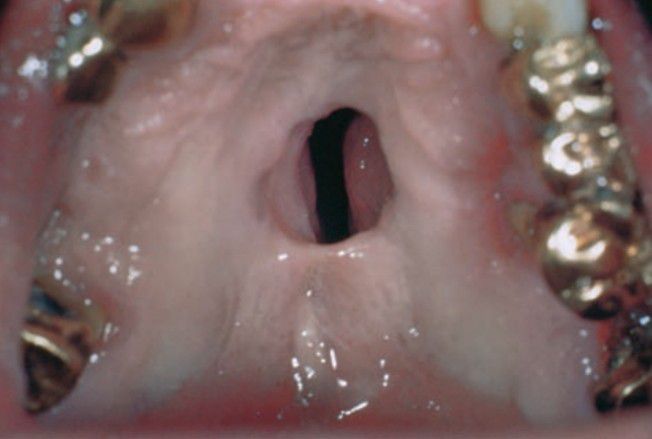

Tertiary syphilis oral lesion

This clinical picture shows gumma formation in palate associated with tertiary acquired syphilis